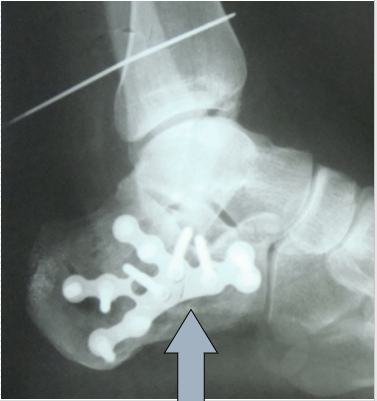

技巧一、跟骨板的形态以及螺钉1.三点固定原理,注意板的方向。

2.还要注意此处2个螺钉,指向内上方,固定载距突。3.螺钉要打满,注意要穿过跟骨内侧壁。

就是这两颗螺钉

Bohler“s角、Gissan”s角如果透视可显示正常。